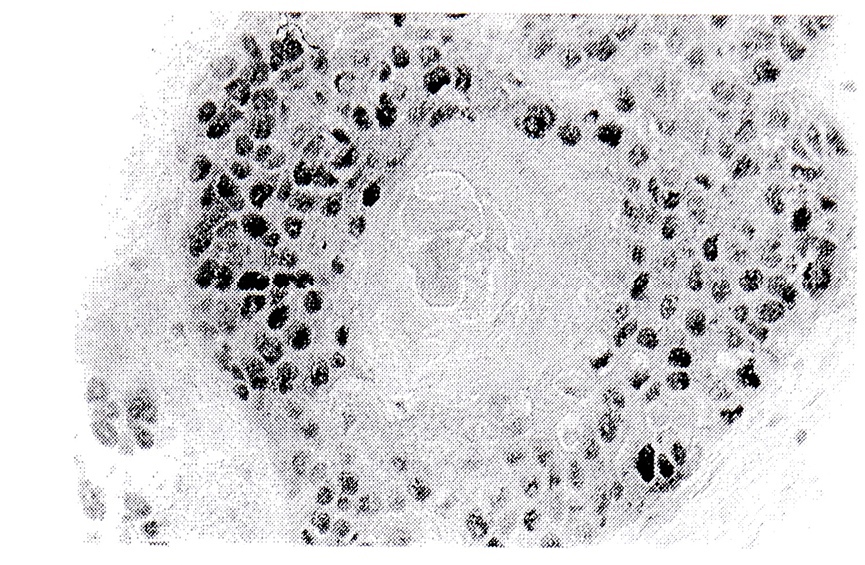

В нормальной слизистой оболочке гортани на PCNA и Кі-67 окрашивались ядра базальных клеток как многослойного, так и многорядного эпителиев. В целом, индексы мечения PCNA и Кі-67 оказались идентичными. Антиген МРМ-2 в нормальном эпителии не был обнаружен. Средний индекс PCNA для исследуемых раковых опухолей составил 62,5±2,8%, а индекс Кі-67 -45,7±3,7%. В высокодифференцированных опухолях (степень дифференцировки Gl) PCNA-и Ki-67-позитивные ядра опухолевых клеток определялись по периферии опухолевых гнезд и вокруг “раковых жемчужин” (см. рис.). Белок МРМ-2 выявлен в цитоплазме опухолевых клеток, находившихся по периферии раковых гнезд.

Окрашивание ядер клеток высокодифферен цированного рака с помощью антител к PCNA выявляет участки опухоли с активной клеточной пролиферацией. Центральная часть ракового гнезда не окрашена. Антитела PC 10, LSAB-метод, хромоген-диаминобензидин. х 400.